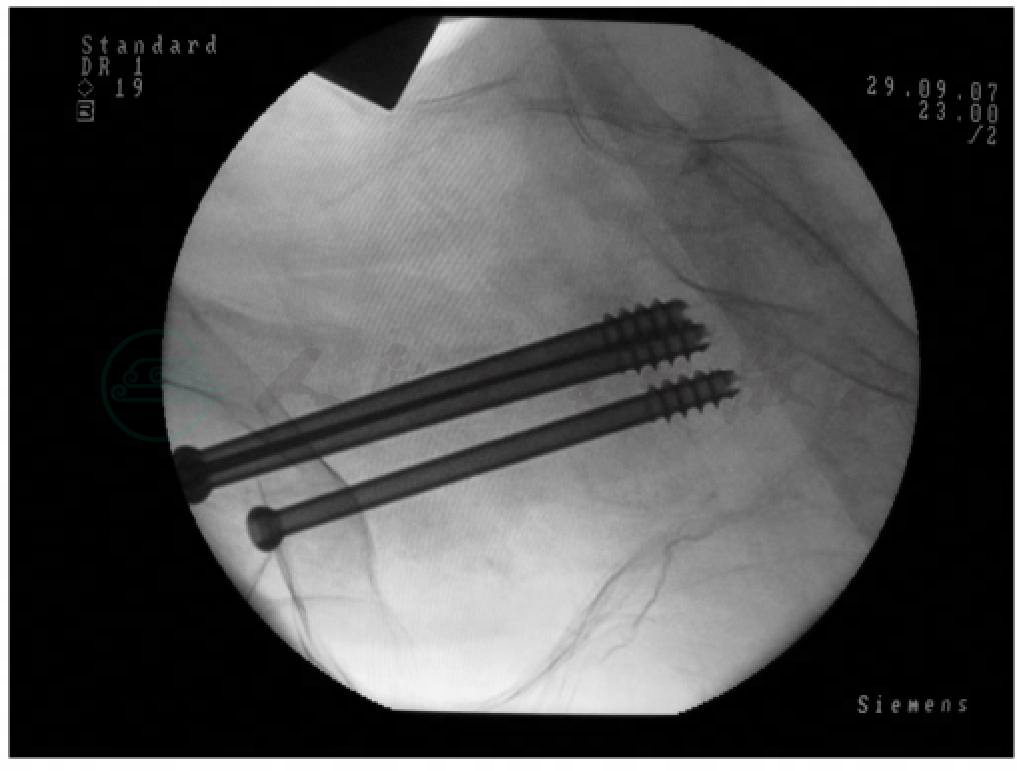

在不影响复位的情况下,可将患肢轻度内旋,使股骨颈在维持正常前倾角的情况下尽量平行于地面,以便于术中的导针及空心钉置入操作。在C形臂X线机透照监控下从大转子下部经皮打进克氏针。以导针针尖探及股骨前后缘,逐渐缓缓轻柔打入,由于骨质疏松,无需很大力量,导针即可轻松打入,打入3枚导针后,C形臂X线机透照位置合适后,测深、钻孔,选择长度合适的AO空心钉3枚沿导针拧入,透视下见接近股骨头时,撤除导针1枚,混合液态硫酸钙人工骨,并沿空心钉钉孔打入(图4),以加强股骨头骨质强度。轮流拧紧,未使用大力适当加压空心钉,C形臂X线机透照复位及固定效果良好(图5)。撤出导针,冲洗伤口,全层缝合皮肤切口,术中出血量约50ml。

图4 术中注入液态硫酸钙人工骨